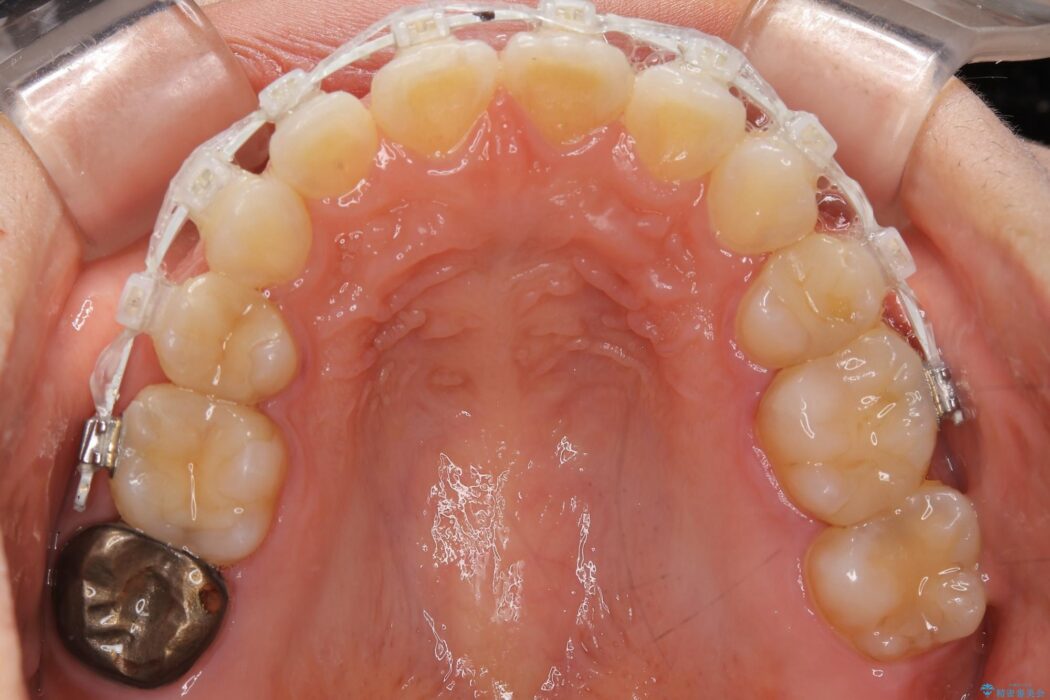

いつもでしたらマウスピース矯正をおすすめするのですが、自己管理の煩わしさから、目立たないワイヤー装置にて矯正治療を行うこととしました。

後戻りの程度としては軽度なので、治療期間としては短く終えることが出来ました。

前歯の正中線も改善され大変満足していただきました。